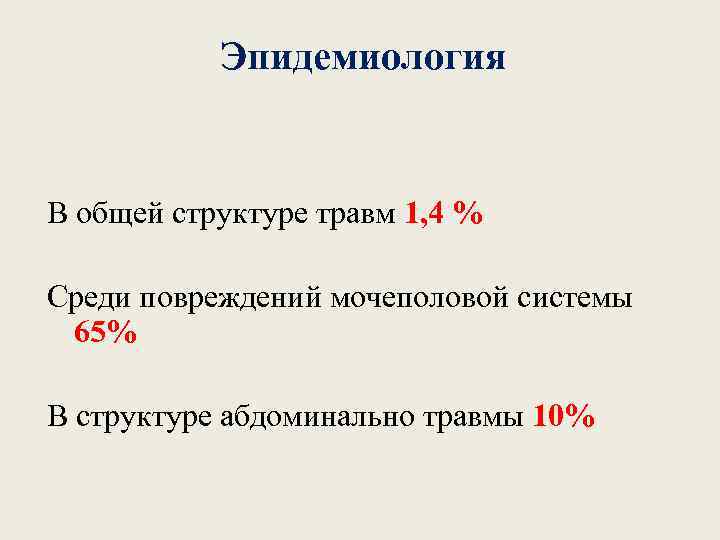

Эпидемиология В общей структуре травм 1, 4 % Среди повреждений мочеполовой системы 65% В структуре абдоминально травмы 10%